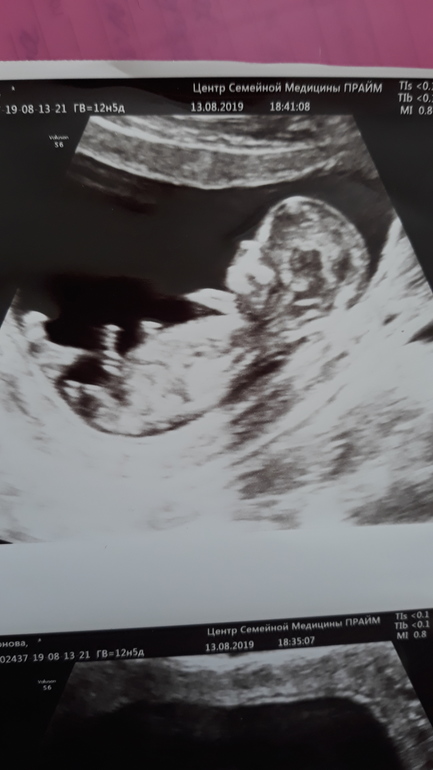

Девченки кто может помочь определить пол,обещают мальчишку а до 2го узи еще месяц ждать.

Ну блин, если на 1м фото половой бугорок а не бедро - то мальчик. Неужели врач не предположил?🤔

на 3й фотографии тоже не понятно что там у него кокички или писюшка🤣